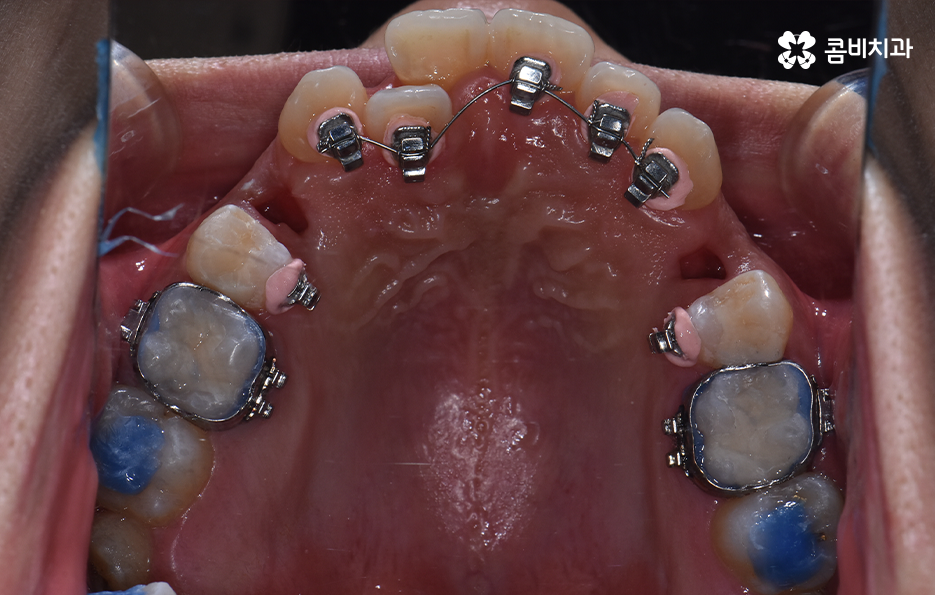

치아교정을 위한 발치교정 과정은 대부분 소구치 라고 불리는 첫번째 작은 어금니를 발치하게 되며 좌우, 위 아래 총 4개의 소구치를 발치한 후에 덧니가 재배열 될 수 있는 공간을 만들기 위하여 우선 송곳니를 후방으로 이동시키고 있어요

그 다음으로는 송곳니가 후방으로 이동하면서 확보된 공간으로 앞니의 배열을 가지런하게 맞추고 있는데요. 앞니의 재배열과 함께 발치 교정으로 인해 빈 공간이 발생한 부분을 없애고 전체적인 치열을 미세하게 조절하게 되는데 발치교정은 치아의 움직임이 많은 편이기 때문에 교합이 잘 맞도록 마무리 배열을 잘해야 하며 그와 함께 치아가 많이 움직이는 만큼 얼굴형의 변화와 입술라인 등의 변화가 클 수 있다는 점에서 치료 후 결과를 잘 예측하여 처음 치료 계획부터 마무리까지 섬세하게 진행하실 필요가 있어요